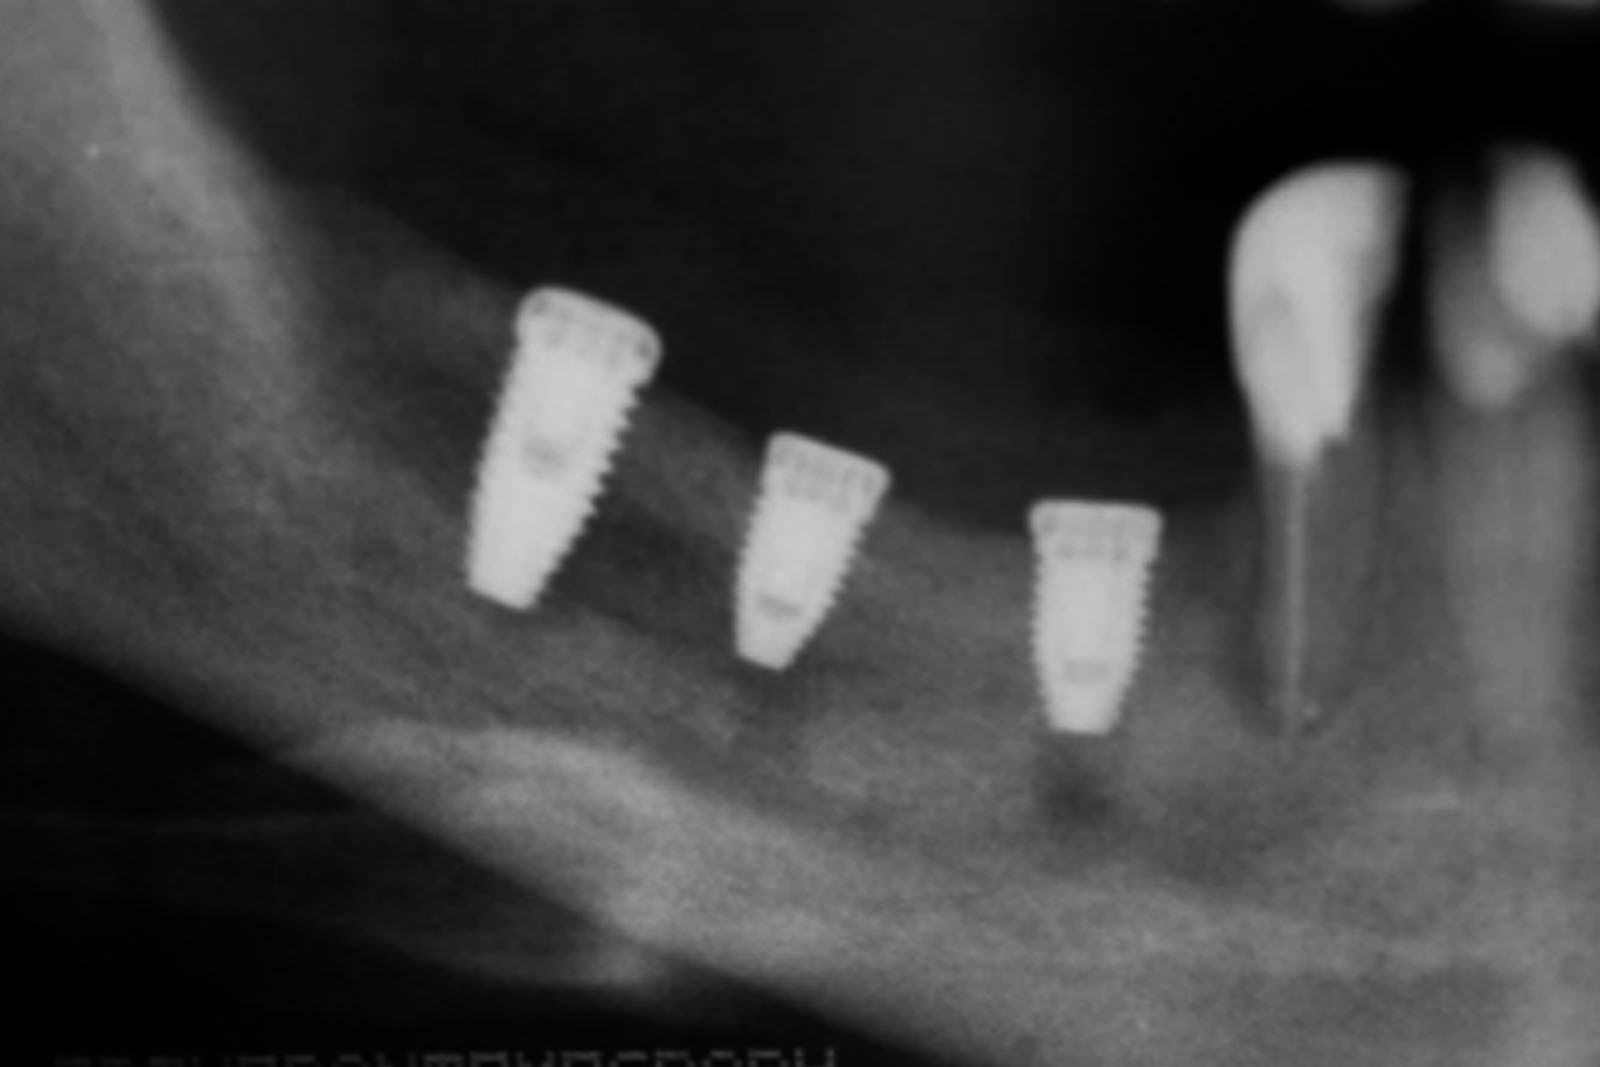

Przed podjęciem leczenia należy określić stopień zaniku kości szczęk oraz żuchwy. W tym celu przeprowadza się badanie kliniczne oraz odpowiednią diagnostykę obrazową pacjenta. Uwzględnia ona zdjęcie panoramiczne OPG jako podstawę dwuwymiarowego obrazowania podłoża kostnego oraz możliwe jest badanie tomograficzne CT lub bardziej precyzyjna tomografia stożkowa CBCT. Opcjonalnie wykorzystywana diagnostycznie tomografia pozwala na bardziej wnikliwą ocenę stopnia zaniku kości w trójwymiarowym, przestrzennym obrazie.

Metoda rekonstrukcji kostnej w oparciu o indywidualnie drukowane siatki z tytanu dla implantacji wszczepów śródkostnych stosowana jest najczęściej jako dwuetapowa. W pierwszym etapie odbudowywana jest kość, natomiast implanty wszczepiane są po okresie 4–6 miesięcy. Na wgojenie implantów oczekujemy od 4 do 6 miesięcy w zależności od miejsca ich lokalizacji. Siatka tytanowa po spełnieniu swojej funkcji rusztowania dla odbudowującej się kości jest następnie usuwana w dniu wszczepienia implantu. Jeżeli kość spełnia odpowiednie warunki, istnieje możliwość zastosowania modyfikacji siatki tytanowej, która umożliwia jednoczesne wprowadzenie implantów wraz z odbudową kostną. Wariant ten skraca czas od pierwszego zabiegu do wykonania gotowych koron protetycznych na wprowadzonych implantach.